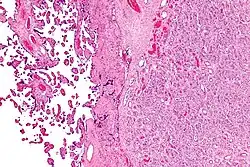

Placenta with an especially large 10cm chorioangioma |

Chorioangioma, or chorangioma, is a benign tumor of placenta. It is a hamartoma-like growth in the placenta consisting of blood vessels,[1] and is seen in approximately 0.5 to 1% pregnancies.[2] It is mostly diagnosed ultrasonically in the second trimester of pregnancy. Large chorioangiomas are known to cause complications in pregnancy, while the smaller ones are asymptomatic.

The origin of chorioangioma is from primitive chorionic mesenchyme. It develops when the blood vessels and stroma undergo rapid proliferation independent of the surrounding tissue. Based on histological features, chorioangioma is classified by Marchetti[5] into three types:[6]

- Angiomatous (vascular) type : This is the most common type of choriocarcinoma. It is distinguished by the presence of numerous small blood vessels.

Histologically, chorioangiomas consist of abundant vascular channels and may be cellular.